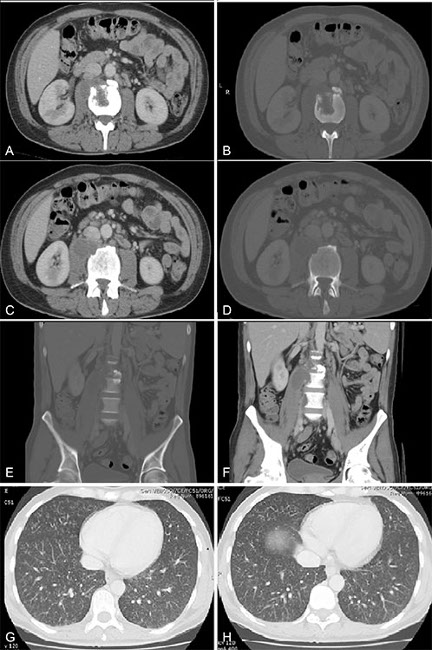

Paciente hombre, 36 años, con antecedentes de VIH, consultó por dolor y aumento de volumen testicular bilateral de aproximadamente 2 meses de evolución, se solicitó TC de abdomen y pelvis por sospecha de tumor testicular. (a, b, c y d) Lesión hipodensa en relación al músculo psoas, con realce periférico de sus bordes, y que parece venir de una lesión osteolítica bien definida que afecta el borde anterior del cuerpo vertebral de L2-L3. (e y f) En el reformateo coronal se puede ver compromiso del disco intervertebral con disminución del espacio discal L2–L3. (g y h) Imágenes predominantemente nodulares centro lobulillares, algunas de ellas con ramificaciones en patrón de árbol en brote, características de TBC.

Los diagnósticos diferenciales para esos hallazgos en TC son variados, dentro de ellos destacan, metástasis neoplásicas, infecciones como brucelosis, infecciones fúngicas y sarcoidosis.8 Las imágenes de tórax, frente a síntomas sugerentes pueden presentar patrones característicos de TBC que ayuden a dilucidar el diagnóstico (Figs. 5g y 5h).